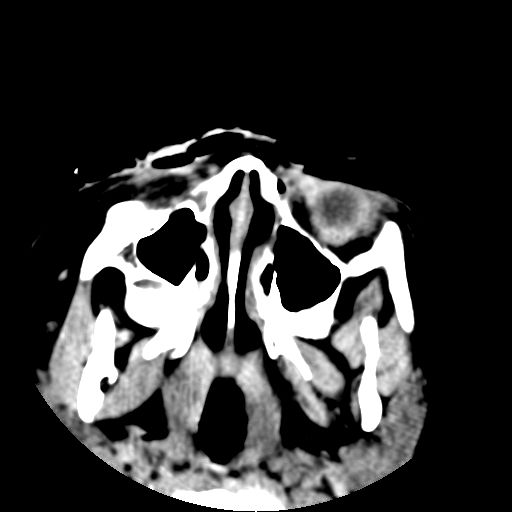

以下是引用深泽交通医院在2009-10-16 8:25:00的发言:[br]右眼环出血伴异物

以下是引用卜一在2009-10-16 15:01:00的发言:[br]右眼球挫裂伤伴异物!

以下是引用拾荒者在2009-10-17 18:38:00的发言:[br]鼻面部皮下积气,右侧睑缘及眼球壁高密度异物影,左侧眼球壁晶状体内侧缘处是圆形低密度影。低密度异物?应提请眼科医生注意。